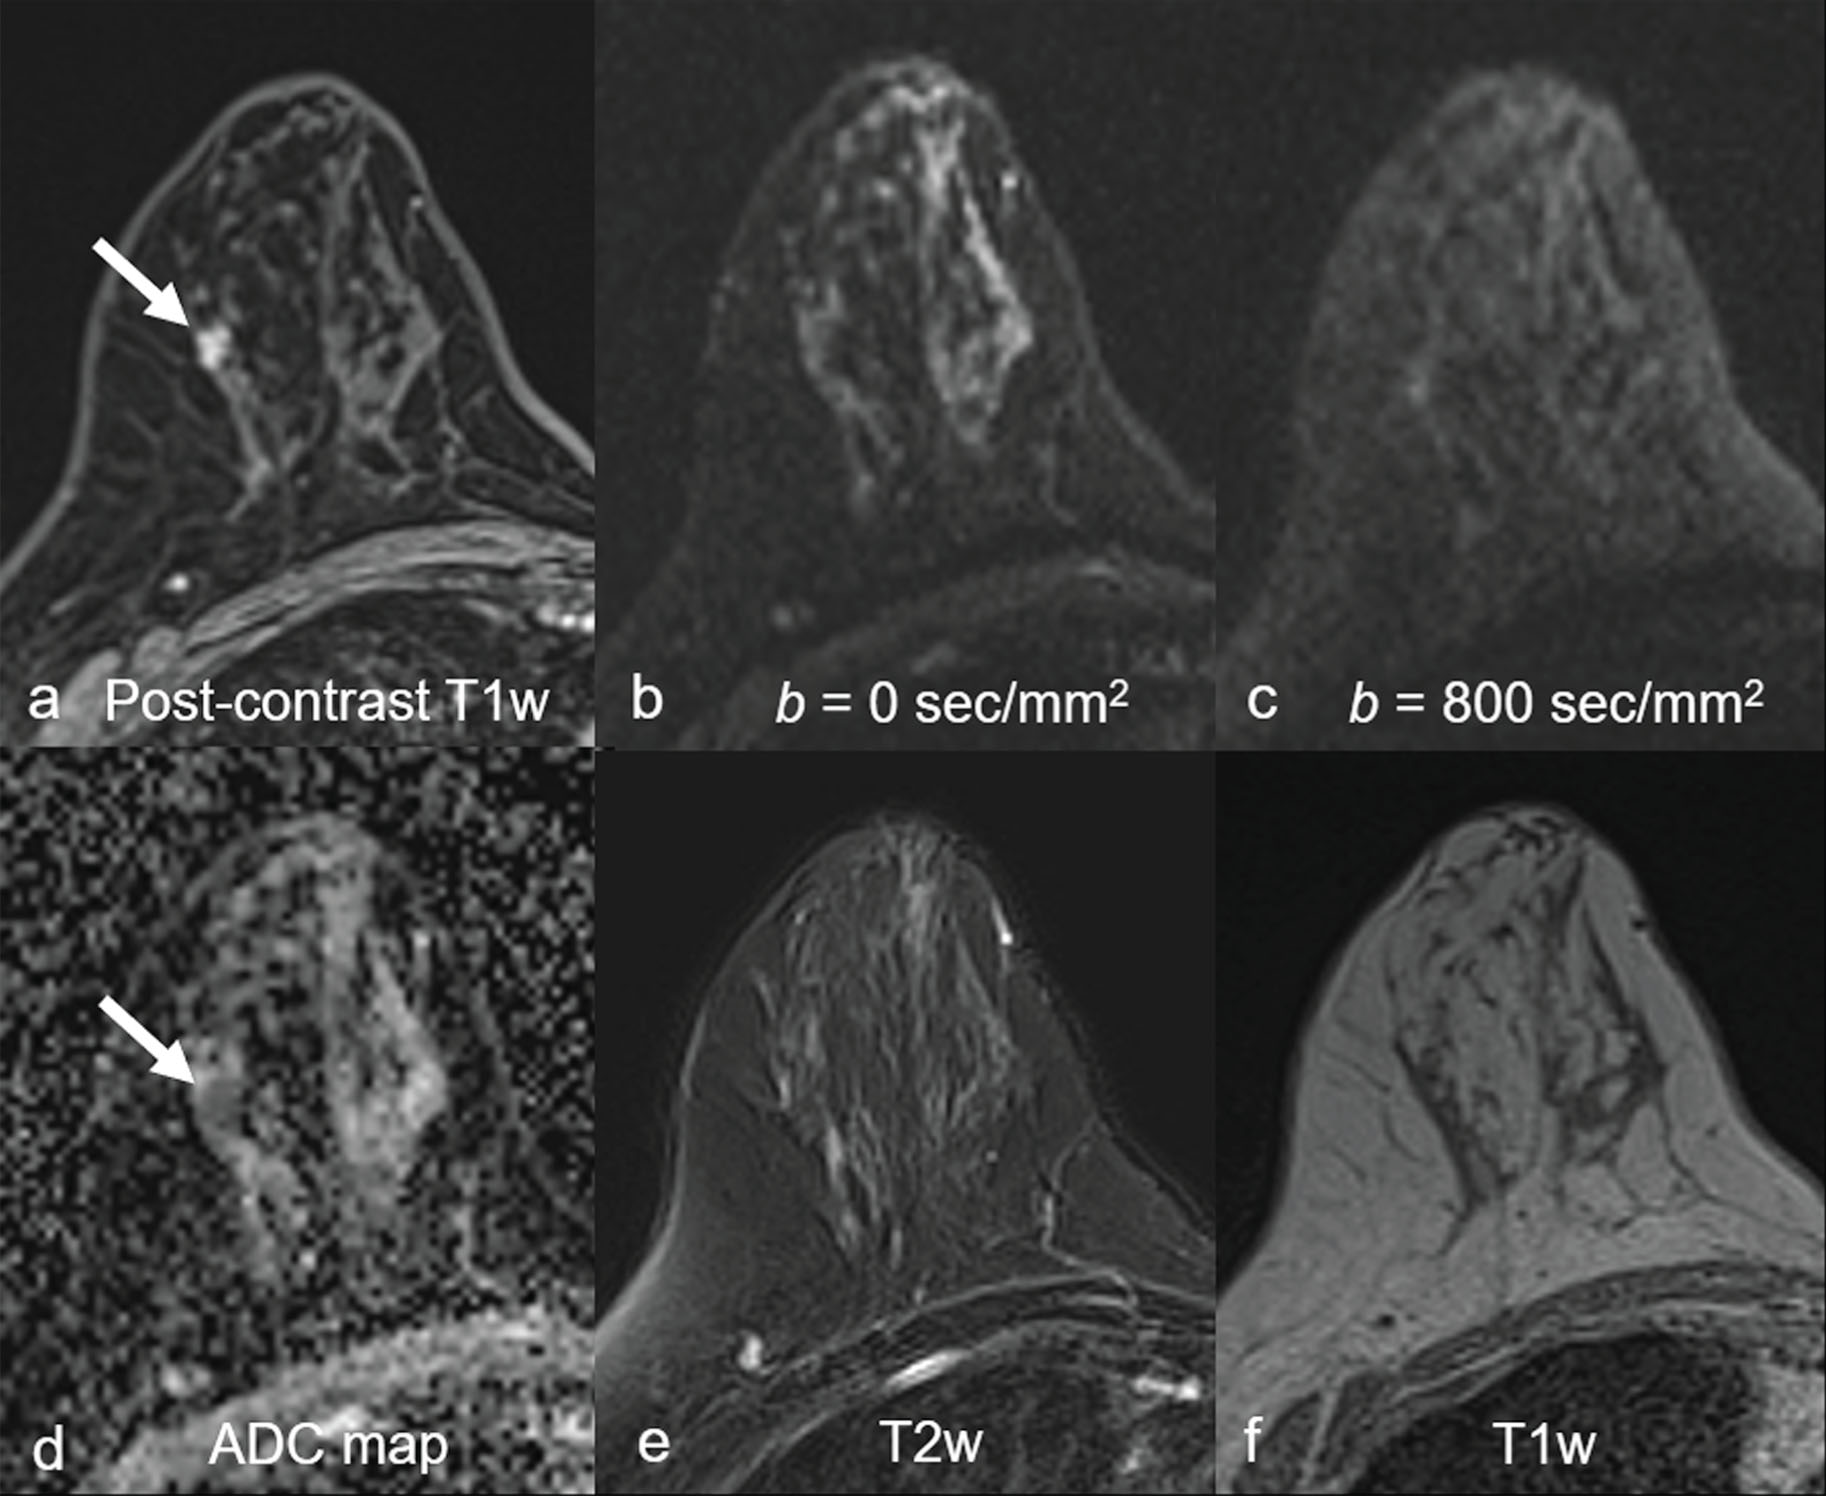

Although dynamic contrast-enhanced magnetic resonance imaging (DCE MRI) is highly sensitive and endorsed by multinational organizations as a supplemental screening tool for high-risk women, widespread implementation of DCE MRI is limited by high cost and uncertain long-term effects of gadolinium retention from contrast administration. In addition, the cost-effectiveness of DCE MRI in intermediate risk patients, such as those with history of breast cancer and dense breasts, remains unclear. Therefore there is great interest in identifying an affordable, unenhanced imaging modality suitable for breast cancer screening. Diffusion-weighted (DW) MRI has emerged as one of the leading options, owing to its short scan time, relative availability and promising sensitivity for identifying breast cancer. DW MRI enables detection of breast malignancies without the need for administering a contrast agent, based instead on microstructural characteristics (e.g., cellular density), as reflected by endogenous diffusional water movement ( Fig. 6.1 ). To date, most experimental and clinical uses of DW MRI have been as an adjunct to DCE MRI in lesion assessment, for preoperative staging of ipsilateral and contralateral breasts, and for evaluating the response to neoadjuvant chemotherapy. However, there is increasing interest in exploring the use of DW MRI as a stand-alone tool for breast cancer detection.

Fig. 6.1, Invasive breast cancer detectable at DW MRI.